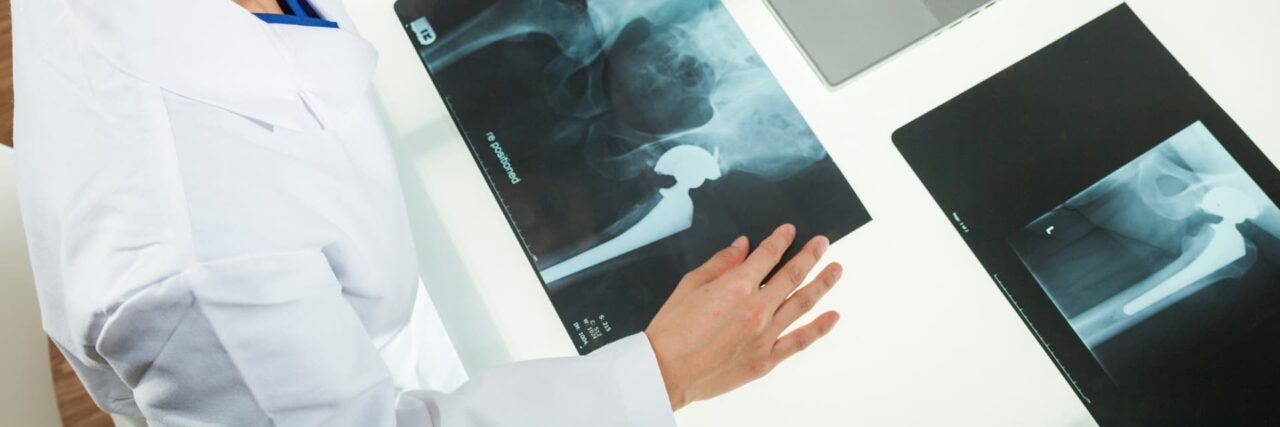

Because like all surgeries, joint replacement procedures do require some recovery time, they are normally only considered after all other non-surgical options have been discussed and/or attempted. Normally, joint surgery provides significant and wonderful results for the majority of patients. At Rothman Orthopaedic Institute, patients have the advantage of being seen by physicians who have actually helped develop and launch joint replacement techniques and who are considered to be well-renowned authorities on the topic of joint replacement

The joint replacement team at Rothman Orthopaedic Institute performs more than 9,000 surgeries every year. Each member of the team is specially trained, has extensive experience and is skilled to perform total joint replacements. Every physician that is a part of this outstanding team of doctors has undergone extensive subspecialty training during his/her residency and fellowship. This team is at the cutting edge of new research in the joint replacement field and Rothman physicians are actually responsible for training other orthopaedic surgeons through international lectures, webcasts, and surgical satellite simulcasts.